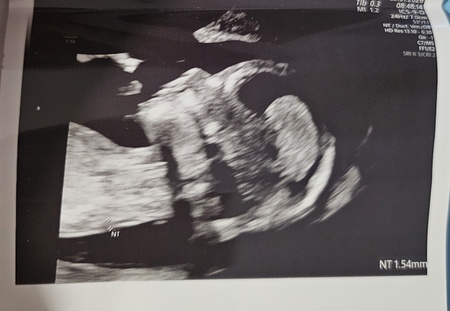

Nasze szczęście